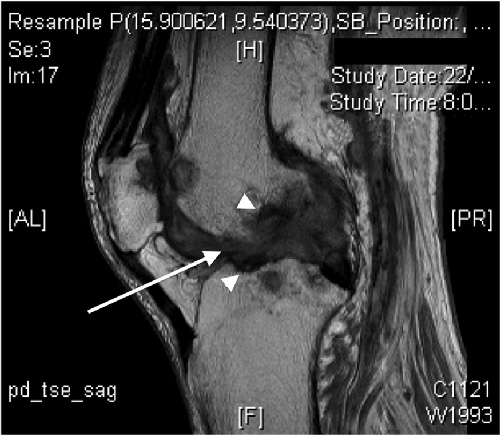

An 81-year-old non-English-speaking Filipino woman with type 2 diabetes mellitus presented with left knee pain and swelling of 18 months’ duration. Her mobility was restricted to less than 2 m because of pain. Synovial fluid obtained by needle aspiration during a recent visit to the Philippines had yielded a white cell count of 12 200 cells/μL (55% polymorphonucleocytes; reference interval [RI] not available) and no bacterial organisms. On her return to Australia, she was referred to an orthopaedic surgeon. Physical examination revealed chronically discharging wounds at previous aspiration sites of the medial and lateral aspects of the knee, which was swollen and tender but with good range of movement. The patient did not have a fever, and her C-reactive protein level was 18 mg/L (RI, < 10 mg/L)]. Magnetic resonance imaging demonstrated florid erosive synovitis, considered most consistent with rheumatoid or seronegative arthritis, although bone oedema was noted, suggesting osteomyelitis (Box 1). Culture of material from the sinuses for bacteria was negative.